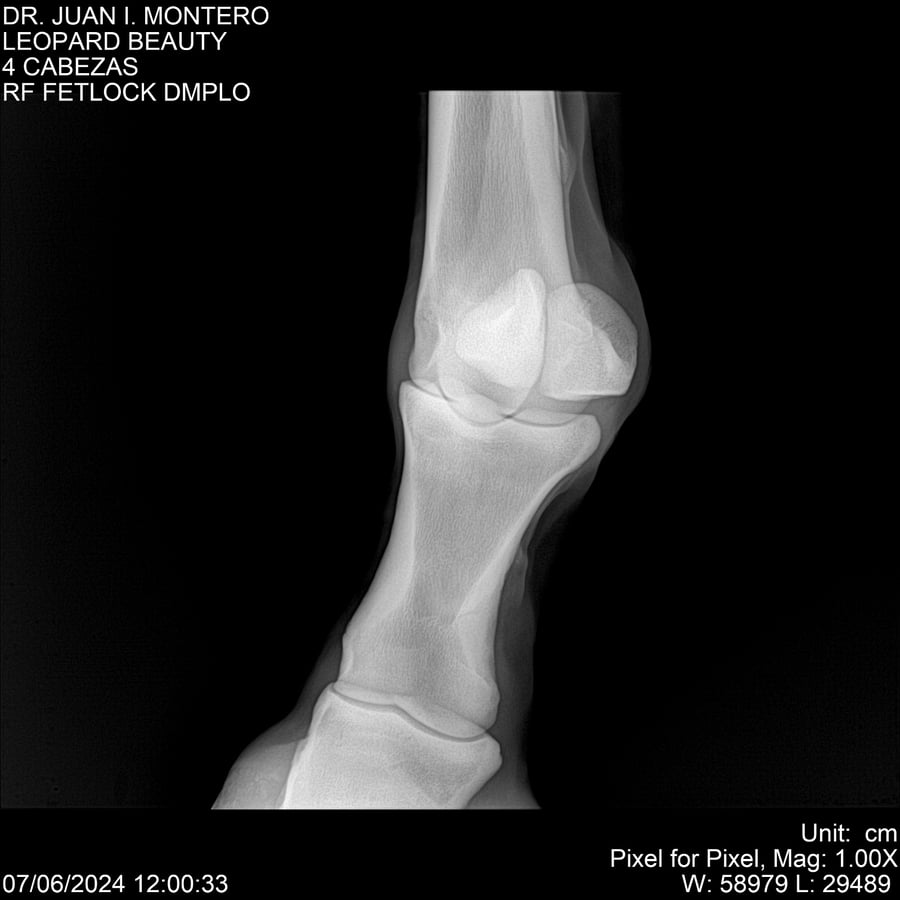

LOTE 16, LEOPARD BEAUTY Lote Anterior Volver al remate Lote Siguiente Ficha Contacto Montevideo - Ficha del Lote Identificador: #281095 Categoría: Yeguarizos Montevideo - 50 Visualizaciones ClicData Contacto Empresa: Abelenda N. R., Walter Hugo Nombre*: Teléfono* : E-mail* : Mensaje Enviar Registrese gratis Este contenido Exclusivo está disponible sólo para usuarios registrados Ingresar